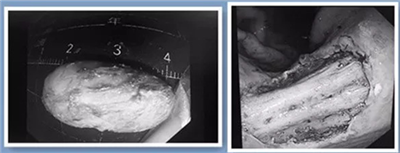

这位郭姓老人因胃胀不适到市中心医院检查,经过超声胃镜和病理活检,医生在她的胃内发现了一个早癌病灶,正好位于胃中部,如果采用外科手术治疗,可能需要做胃全切术,会给患者带来极大的损伤。在医生的建议下,老人接受了胃镜下早癌病灶切除治疗方法。医生采用超级微创ESD技术,从粘膜下将所有癌变病灶“一锅端”。术后,患者恢复良好,住院观察几天即可出院。

市中心医院内镜中心主任袁胜春介绍,这一术式是中心医院在全市率先开展,目前已经成功实施了数十例。她提醒大家,虽然内镜下粘膜剥离术对于消化道早癌手术治愈率非常高,但一般只适用粘膜下浅层的早期癌变。从临床来看,还存在一些患者发现自己身体内有肿瘤的时候,病情已经到了中晚期,错过了做粘膜剥离术的机会。因此,早期筛查、早期诊断、及早干预对消化道肿瘤的治疗至关重要。每个人都应当养成定期体检的好习惯,特别是超过40岁、有消化道肿瘤家族史、萎缩性胃炎、腺瘤等癌前病变的,最好定期做胃肠镜检查,这样才能早发现、早治疗。